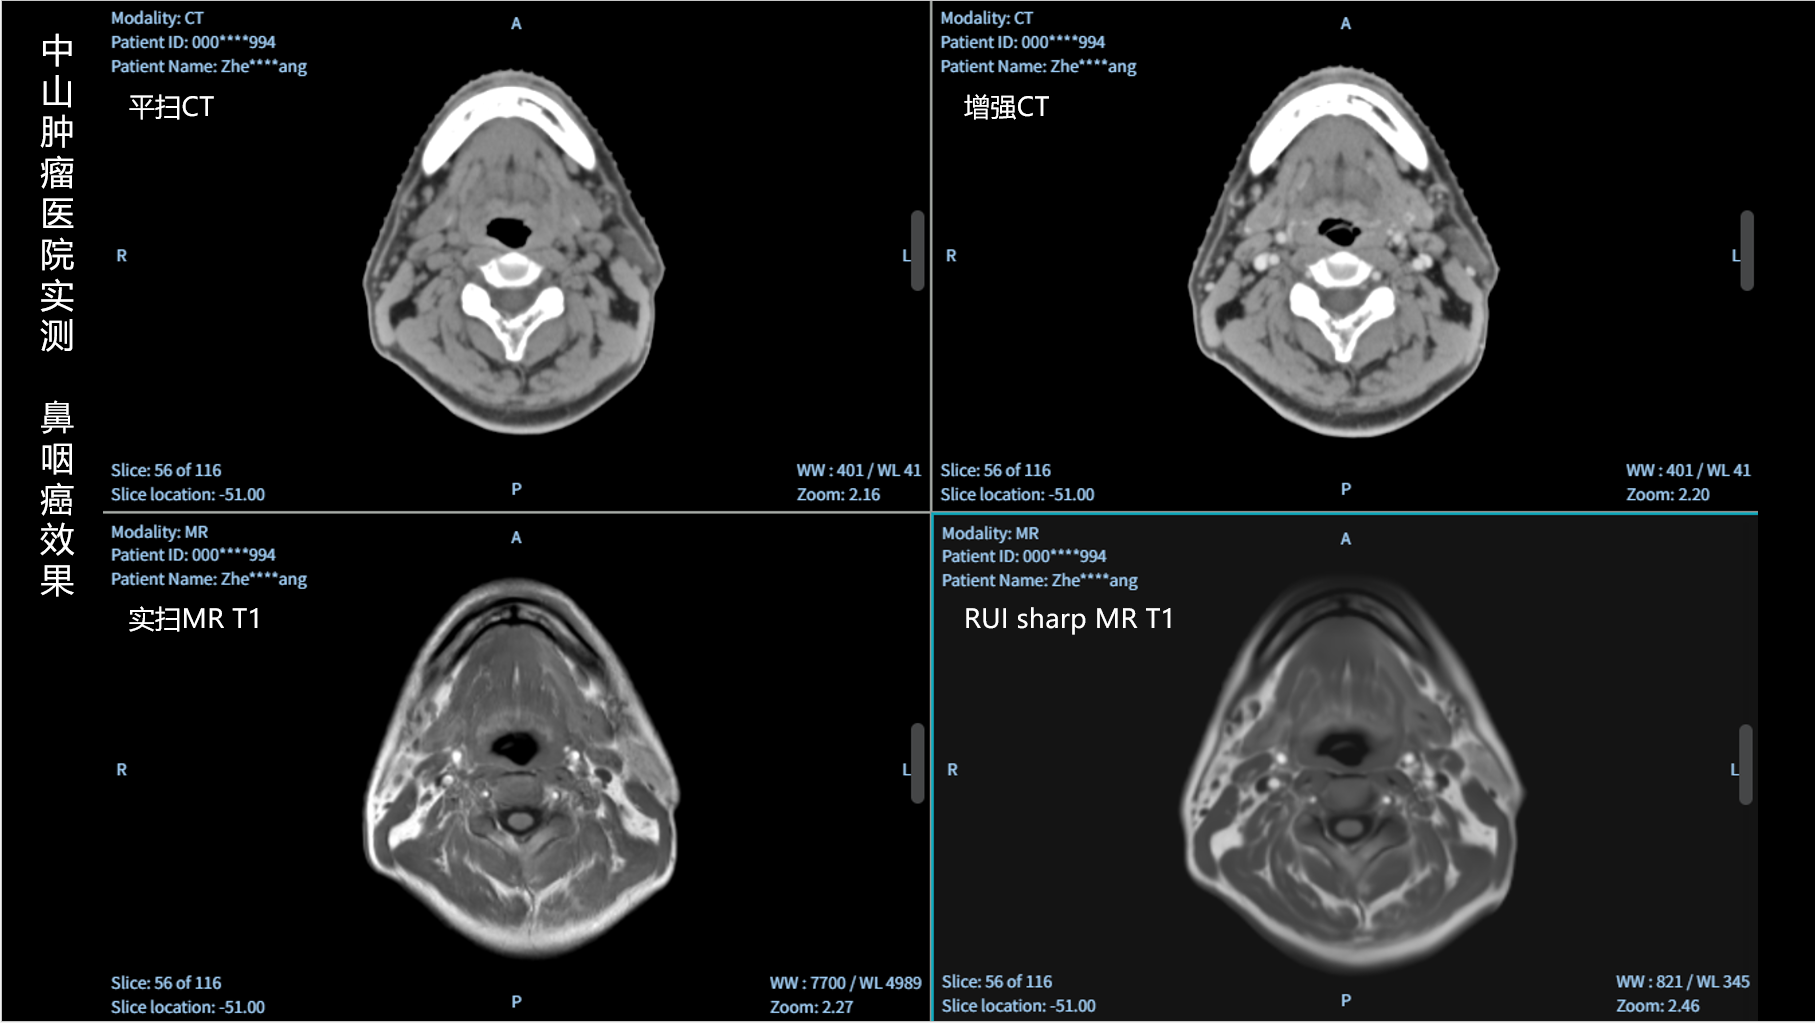

RUI sharp H(锐影)可在不依赖MRI的前提下,显著提升头部CT图像的软组织分辨率,为临床提供更高质量的辅助信息,尤其适用于MRI资源受限或较难配准的头颈部放疗感兴趣区勾画场景。

可大幅提高头部CT影像软组织分辨率,使肿瘤和周边器官显示更清晰,为放疗靶区勾画提供参考。

无需图像配准,CT和锐影图像同源,可匹配、叠加、"淡入淡出"显示。